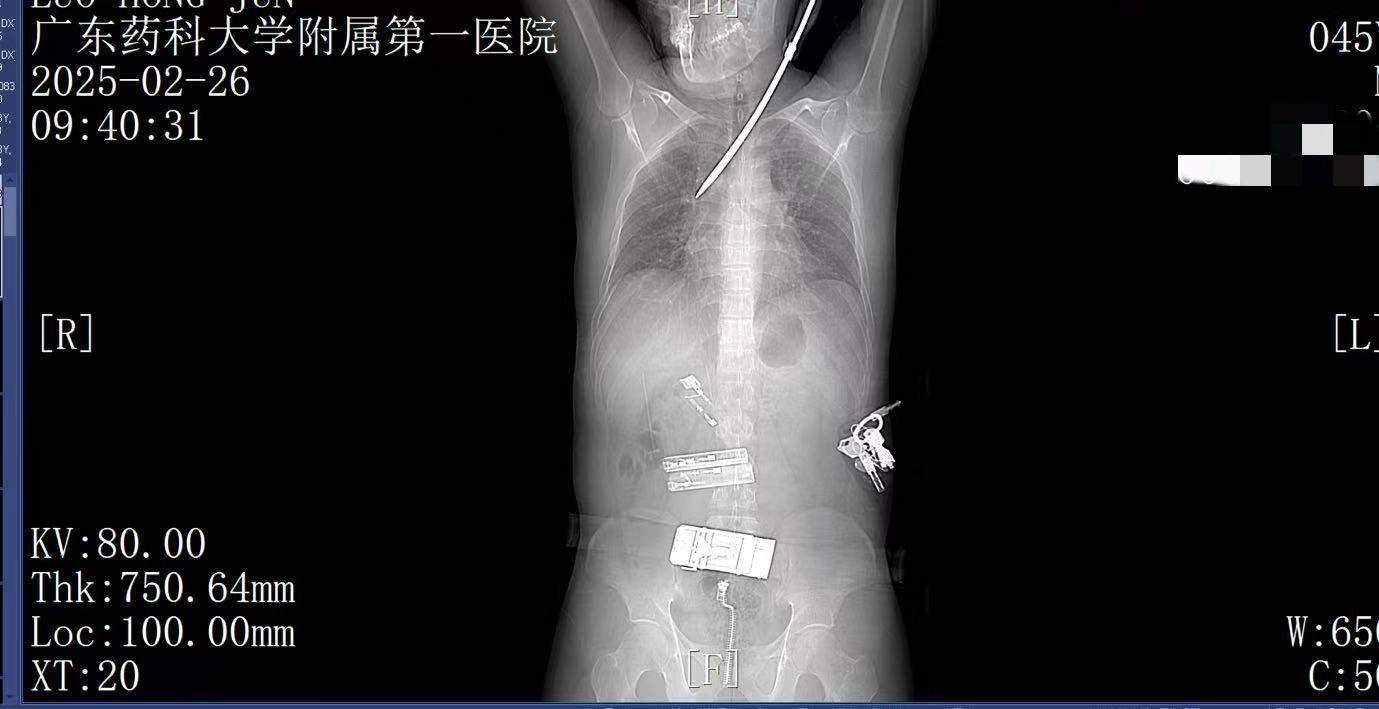

2月26日上午9时许,44岁的电梯工人罗师傅(化姓)正在广州某工地弯腰工作,突然一把螺丝刀从20多米高处坠落,刺中罗师傅的胸背部如何利用行业消息去炒币。罗师傅当即疼痛难忍,呼吸困难。工友立即呼叫120。一场惊心动魄的生死救援立即展开。

9:22,广东药科大学附属第一医院救护车到达现场,查看患者伤情后,黄业君主治医师立即固定好螺丝刀,避免再次移动损伤神经血管,并马上电话联系医院后方,医院急诊科主任曾育辉立即通知心胸外科、脊柱外科等相关科室紧急会诊如何利用行业消息去炒币。

9:39,救护车到达医院大门,院内急救团队已经做好准备如何利用行业消息去炒币。在紧密监护的情况下,全程采用绿色通道。到达医院时,罗师傅已经面色苍白,呼吸急促。螺丝刀已深深刺入罗师傅右肺,随时可能因大出血而危及生命。

9:41,快速完成头+胸+腹部CT检查,经多学科会诊,明确螺丝刀异物刺入肺部如何利用行业消息去炒币。CT显示螺丝刀紧贴肋间血管、上肺后段动脉,尖端距右肺门仅2厘米,一旦贸然拔出螺丝刀,极有可能引发大出血,导致失血性休克甚至死亡,必须紧急手术。

无影灯下,麻醉科陈建颜主任团队精准实施单肺通气保障氧合,心胸外科肖海平主任团队沉着冷静,采用单孔胸腔镜技术进入胸腔,一步步地分离受损组织,仔细止血,避开重要血管如何利用行业消息去炒币。医护默契配合,成功将插入患者体内达13厘米的螺丝刀完整取出。手术顺利完成,罗师傅的生命体征逐渐恢复平稳,成功脱离了生命危险,大家心里悬着的石头终于落地。